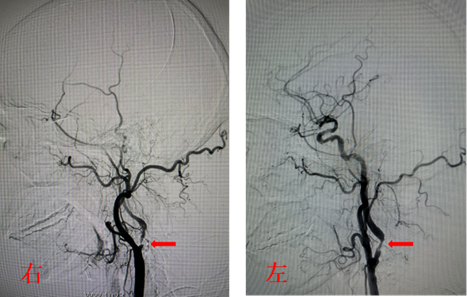

手术由神经内科孙奉辉主任和孙际典副主任医师实施,术中造影显示入颅的四条动脉(双侧颈内动脉起始部及双侧椎动脉开口)均有重度狭窄,尤其是右侧颈内动脉起始部为次全闭塞(如图),且为此次缺血性脑血管事件的责任血管,如不及时处理,病情可能随时加重。根据患者病情及家属诉求,决定先行右侧颈内动脉支架置入术,支架后血流恢复良好(如图)。术后患者症状完全消失,无明显不适。

右侧颈内动脉起始部次全闭塞,远端显影浅淡,左侧颈内动脉起始部重度狭窄